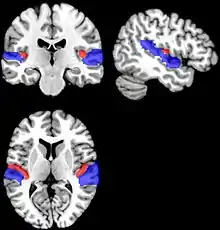

As brain regions particularly crucial in speech production are disconnected, it may cause persistent dysfluency. If the dysfluency continues into adulthood, researchers have found the basal ganglia and the attrition of white matter below the sensorimotor cortex in the brain as contributing factors.[15] In addition, because connections between the motor cortex and the basal ganglia are essential for speech production, dysfunctions in this area could be a cause of persistent developmental stuttering (PDS). PDS is the persistence of stuttering and other dysfluencies into adulthood. Researchers have proposed therapies to assist in speech production improvement, such as fluency shaping therapy.[15]